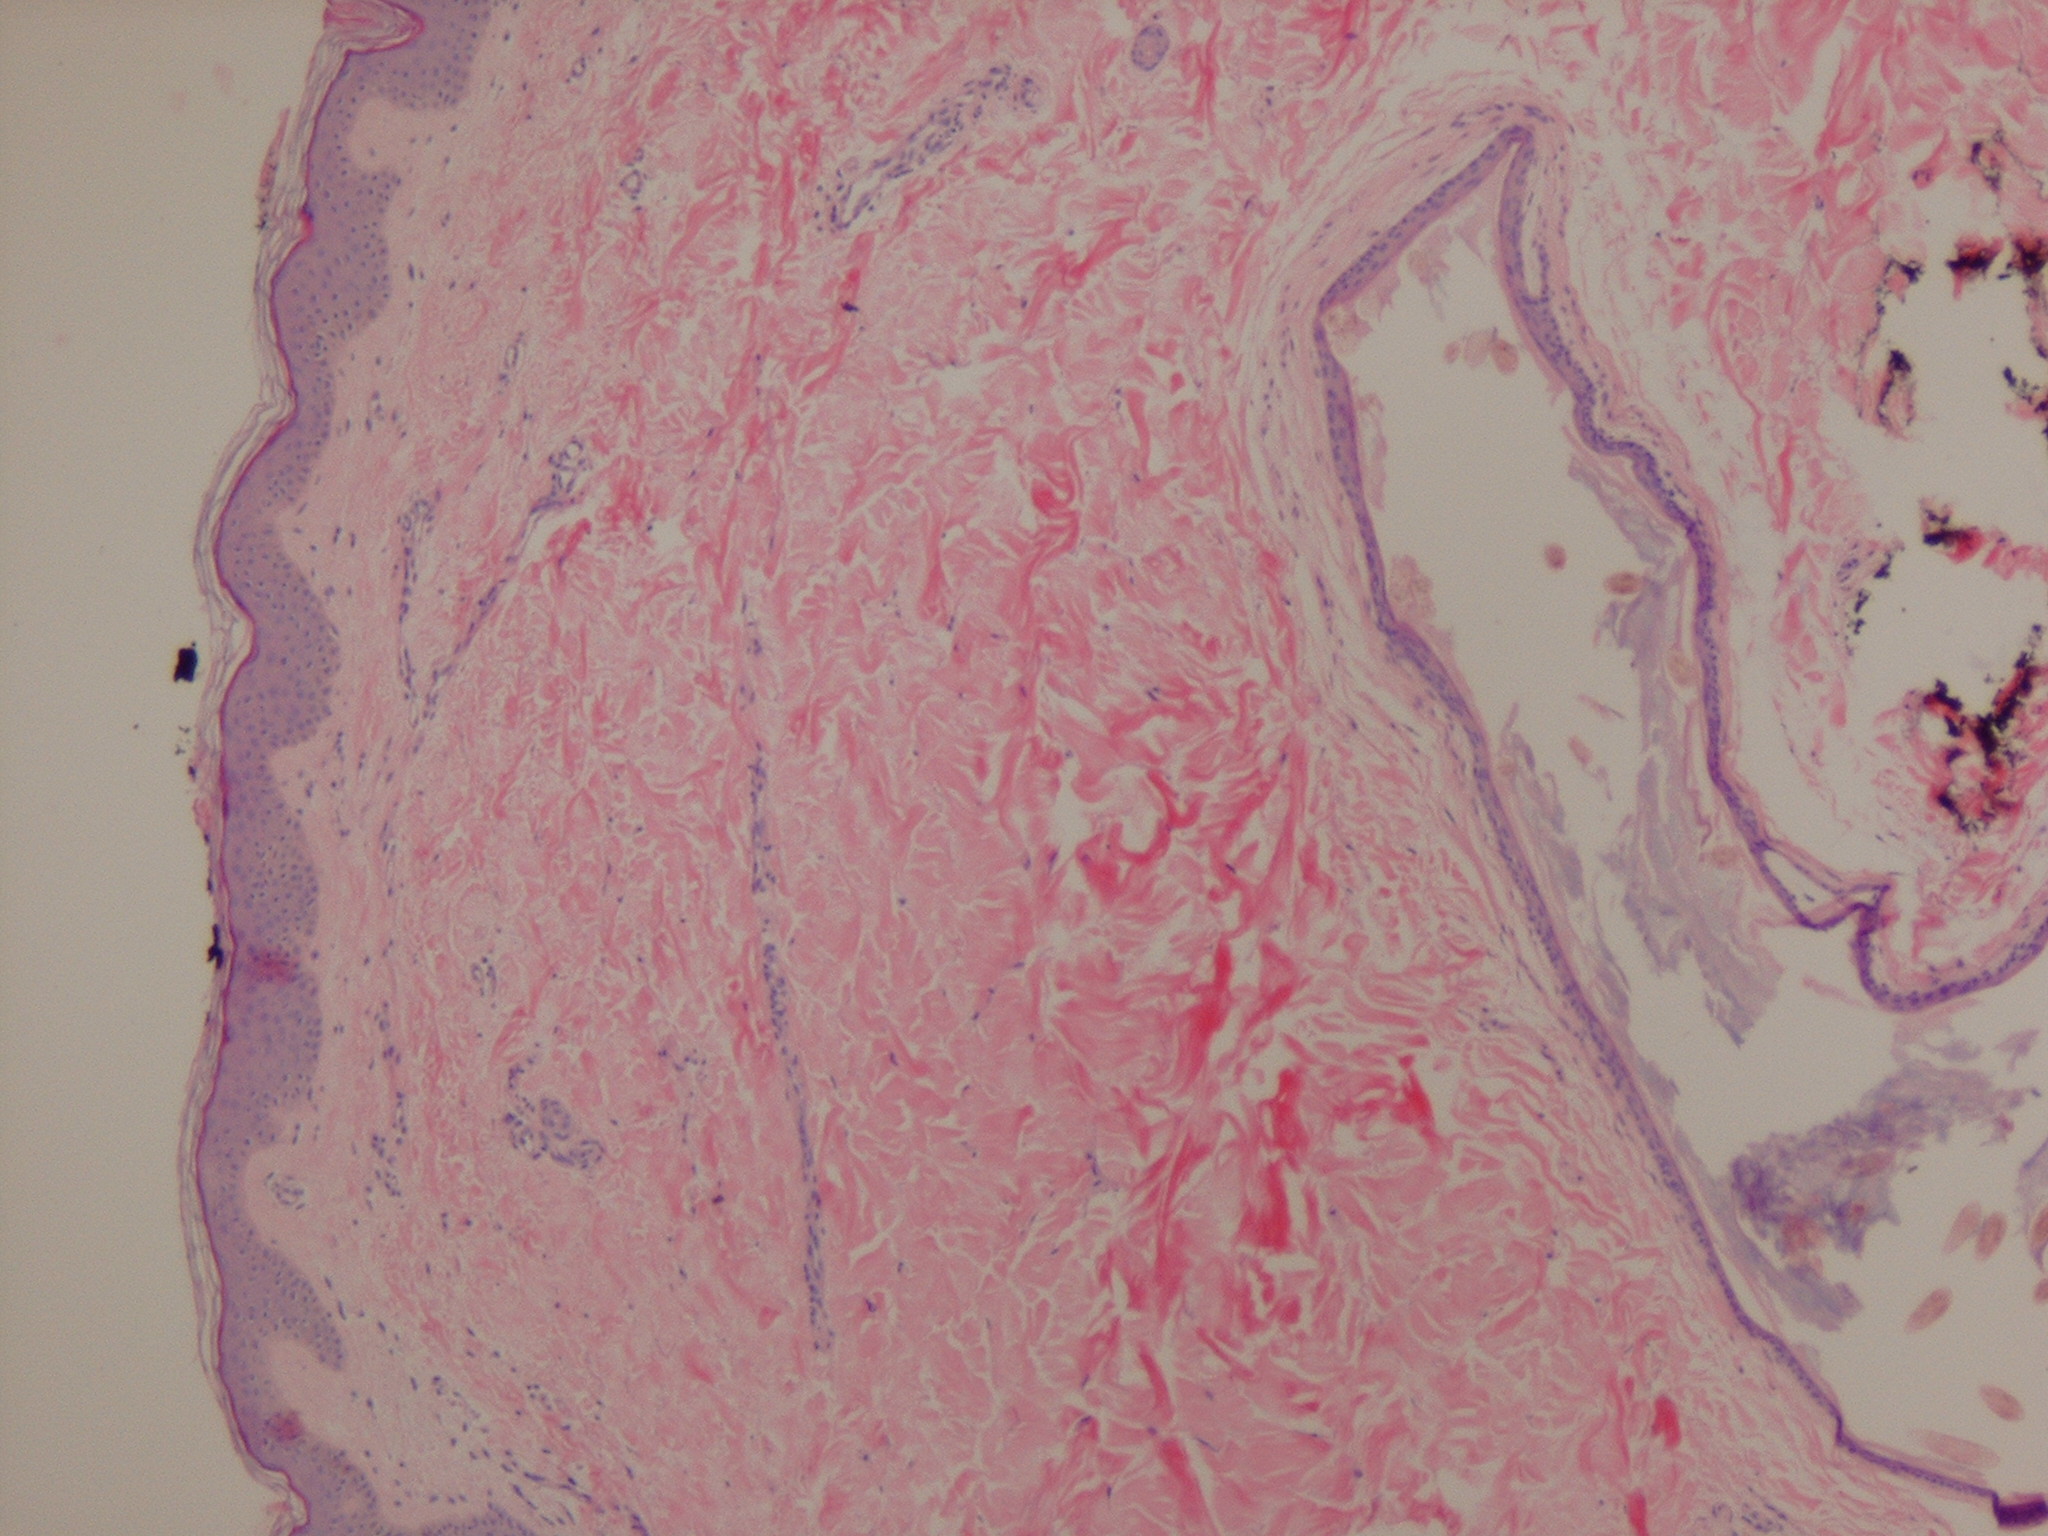

Representative photomicrograph of a steatocystoma stained with Vellus Hair Cyst Reddit It's caused by a genetic quirk that causes. My current shortlist, having researched this extensively i am pretty sure it's trichostasis spinulosa, along with vellus hair cysts. Eruptive vellus hair cysts, which result from a rare abnormality of the vellus hair follicles. These cysts develop as red or brown bumps, usually on your chest, forearms and trunk. Funnily enough, no. Vellus Hair Cyst Reddit.

Histopathologic result of the biopsy of a vellus hair cyst in a child Vellus Hair Cyst Reddit What is an erruptive vellus cyst: Eruptive vellus hair cysts, which result from a rare abnormality of the vellus hair follicles. Basically, it's a small ball of sebum and impacted/ingrown peach fuzz. They are usually seen in children,. Eruptive vellus hair cyst (evhc) is a rare follicular developmental abnormality of the vellus hair follicles. Eruptive vellus hair cysts commonly present. Vellus Hair Cyst Reddit.